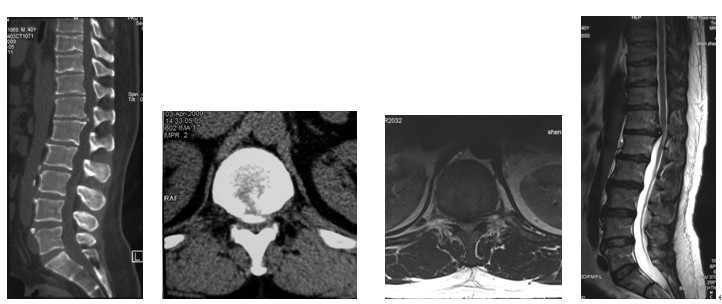

4. 典型病例:病例1,患者男性,40岁,司机。主因胸腰背部疼痛3年,肛周麻木、性功能减退并伴双足下垂2年,症状加重且二便肥力、无法工作1年入院。入院查体:一般情况良好,体胖、体重105kg。步态不稳,步行缓慢。胸腰段脊柱背部轻压痛,无放射。双侧股四头肌力IV级,双侧胫前肌力I级,双侧足下垂。鞍区感觉减退,无病理征。双侧跟、膝腱反射消失。血化验检查正常。X线平片显示T12~L1椎间隙明显变窄。CT显示T12~L1椎间盘突出并椎体后缘离断。MRI显示T12~L1椎间盘呈中央型突出,椎管狭窄,脊髓明显受压变形。入院诊断:T12~L1椎间盘突出症伴椎体后缘离断,马尾神经损害。术前检查完成后,在气管插管全麻下行上述经极外侧入路T12~L1椎间盘切除手术治疗,整个手术过程顺利,无术中及术后并发症发生,术后1周顺利出院。出院时,其双侧股四头肌、胫前肌肌力已分别恢复至V级和III级;鞍区感觉减退亦有明显好转。术后显示T12~L1突出之椎间盘及离断之椎体后缘已被完全切除,椎间融合器及椎弓根螺钉位置佳,脊柱局部生理曲度良好(图2a~2l)。病例2,女性患者,59岁。主因间歇性跛行,双下肢无力3年入院。入院诊断:T11椎体后上缘骨软骨瘤。以与病例1相同的术式行椎体骨软骨瘤的彻底切除(图3a~3l),无手术并发症发生,术后患者下肢症状明显改善。

图3a~3d. 典型病例2患者术前均显示为T11椎体后上缘骨软骨瘤,分明显突入椎管, 脊髓明显受压.